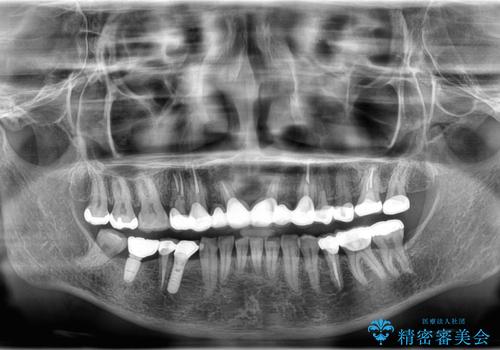

- 右上の歯に異和感があるとの事で来院した患者様です。

検査の結果、歯根破折が認められたため、抜歯即時インプラント(1DAYインプラント)を行いました。

1日で抜歯、インプラント埋入、骨補填材を填入し仮歯【1DAYインプラント】までを数時間で行いました。

術後もほとんど痛みがなく経過も良好です。